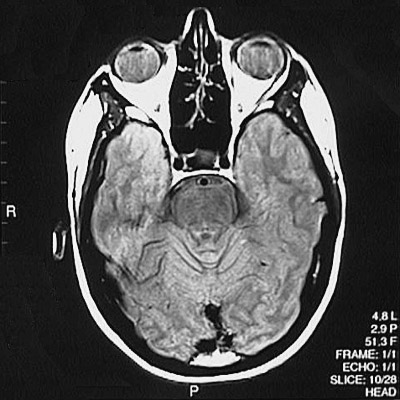

This is a normal axial proton density MRI scan demonstrating the temporal lobe and occipital lobe and basilar artery and internal carotid artery and basis pontis and aqueduct of Sylvius and cerebellar vermis and ethmoid sinus and pituitary and globe of eye and lens of eye.